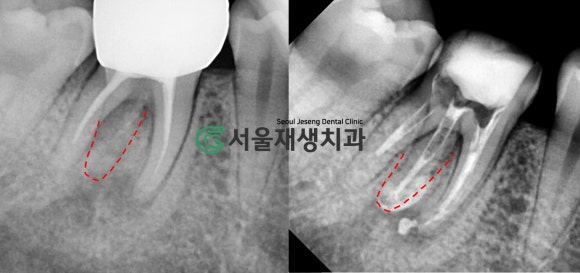

빨간 점선으로 표시된 것 보이시나요?

바로 치료되지 않고 남아있는 뿌리입니다.

어금니에는 신경줄이

여러 개 있기 때문에,

간혹 1~2개를 놓치게 되는 일이 있습니다.

재신경치료를 하게 되는

여러 이유 중 가장 큰 비중을

차지하고 있지요.